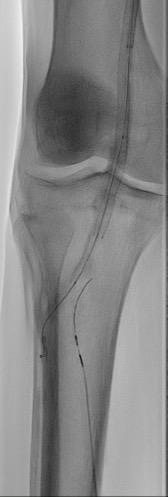

Case review: Arterial example

Here, we present a case of a patient with severe ischemic rest pain and an ankle-brachial index (ABI) of 0. The patient was a prior smoker who had multiple prior interventions for critical limb ischemia (CLI) and tissue loss. In 2021, the patient had a second femoral-to-tibial artery bypass and was lost to follow-up.

On angiogram, there was redemonstration of superficial femoral artery and popliteal artery stent occlusion, and chronic occlusion of both the anterior tibial and posterior tibial target bypasses. There was no arterial reconstitution of viable open or endovascular target vessels in the foot.

Deep venous arterialization (DVA) was performed using the Pioneer Plus catheter for IVUS-guided arterial re-entry (see Figure 1). Visualization of the popliteal artery re-entry target by IVUS allowed for rapid crossing from the posterior tibial venous access site (see Figure 2).